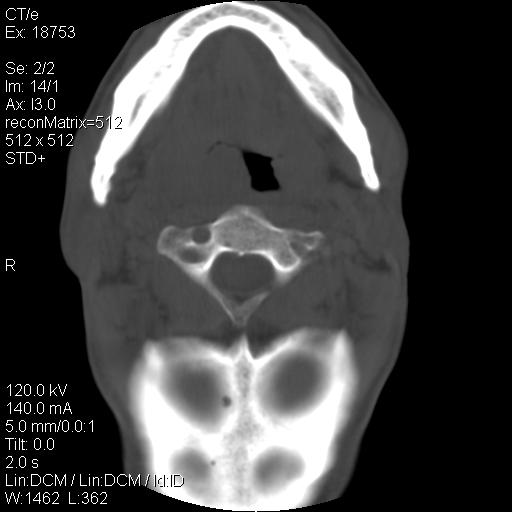

标题: CT21693:男 58岁 右侧咽部疼她2天余 PE:右侧扁桃体肿大 压痛 [打印本页]

标题: CT21693:男 58岁 右侧咽部疼她2天余 PE:右侧扁桃体肿大 压痛

1 弥漫性肿胀,与周围组织分界清晰,发病急,有明显症状,考虑急性炎症【wbc]

弥漫性肿胀,与周围组织分界不清,发病急,有明显症状,考虑:感染性病变!

右化脓性扁桃体炎症伴咽后壁脓肿形成.